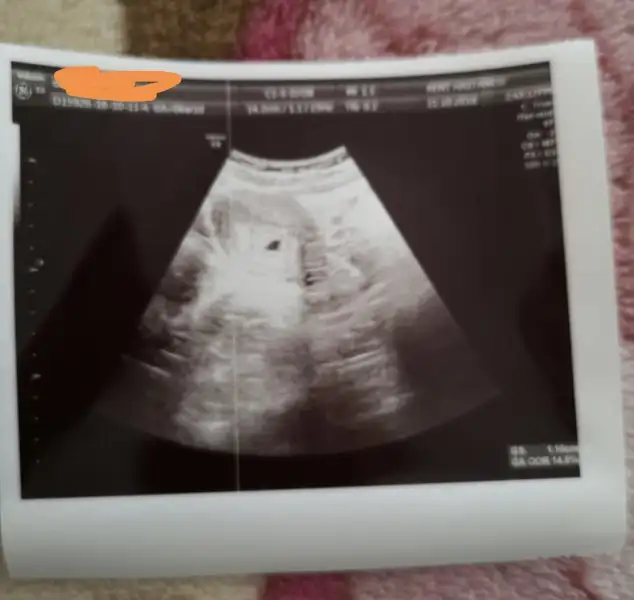

Günaydın kızlar :KK200: bugün kalp atımını duyduk biz de şükür :nazar: doktor herşey normal gelişim tam sata uyumlu dedi

Kalp atımını kısaca dinletiyorlar bebeğe zarar verebilirmiş olsun bu kadarı da yetti darısı heyecanla bekleyen tüm anne adaylarına inşallah

Bugün sonunda kesemizi gördük ama kalp atışı ve bebek için 10 gün sonraya randevu aldık...